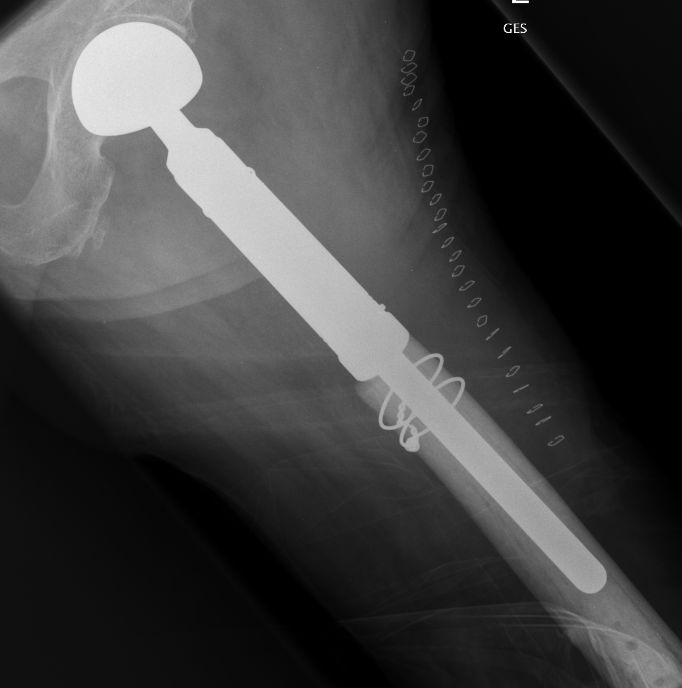

| Subtrochantäre Fraktur | 61-jähriger Patient mit schlecht differenziertem Adenokarzinom der Lunge. Jetzt pathologische Fraktur per-/subtrochantär links. Ausgedehnte Tumorosteolyse. ![]() |

Therapie: Schaftendoprothese.![]() | ||